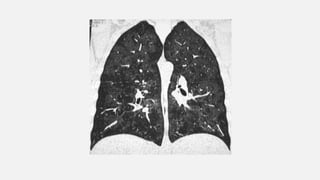

• 31.

Diffuse Air-space Nodules This appearance is seen in patients with endobronchial spread of infection such as : • Tuberculosis (TB) or Mycobacterium avium complex (MAC) bacterial • bronchopneumonia • viral pneumonia (cytomegalovirus [CMV], measles) • invasive mucinous adenocarcinoma with endobronchial spread • pulmonary hemorrhage • aspiration.